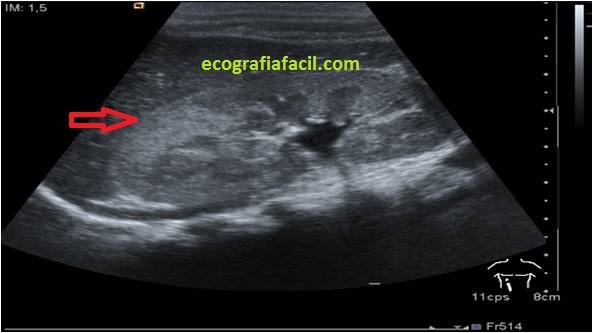

2. Alteración de la ecogenicidad. Como ves en las imágenes que te pongo a disposición, compara la normalidad con la patología y juzga…

3. Compresión del seno renal.

4. Masa o masas mal definidas.

Normalidad:

Semiología de la Pielonefritis, que puede afectar en diferentes grados, puede ser que no haya afectación, puede que sea una afectación parcial o de sólo un área del riñón, que se verá más hiperecogénica que el resto del Riñón…Mira: